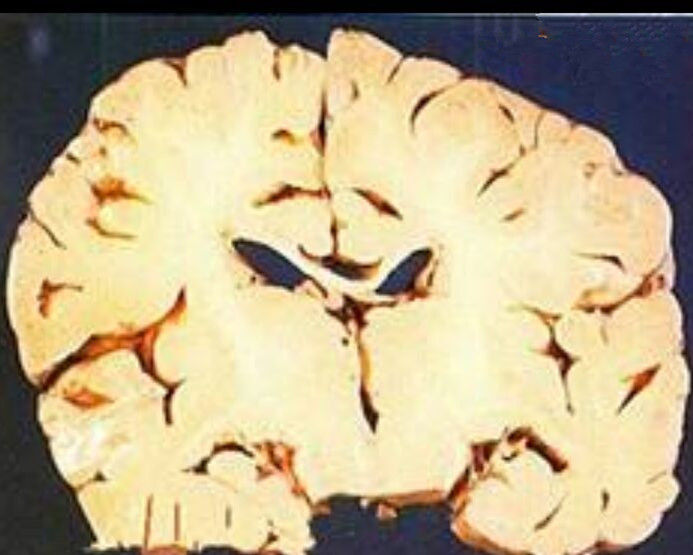

細菌性腦膜炎的解剖

細菌性腦膜炎的腦